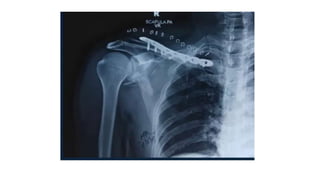

MANAGEMENT : CLAVICLE FARCTURE

• Should be fixed if displaced

• Reduces risk of non union

• Reduces tension on brachial plexus

• Restore anatomical relationship

• Improves function

• ? may reduce & stabilise glenoid fracture